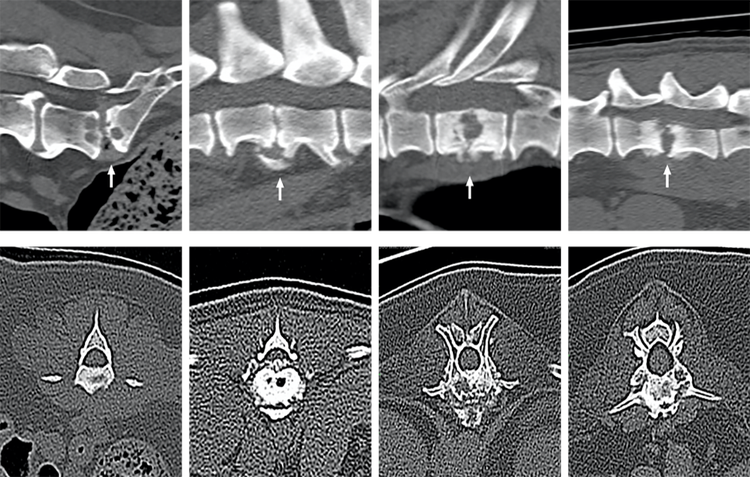

To date, MRI has been the imaging modality of choice, with consistent CT imaging features of Discospondylitis in dogs and cats not previously reported in detail. However, with the increased availability of CT in clinical practice, the research set out to examine CT features that could support the diagnosis of Discospondylitis.

- MRI is currently the imaging modality of choice for Discospondylitis. However, with the availability of CT in clinical practice, this research was warranted. CT presents some advantages over MRI in the diagnosis of Discospondylitis such as excellent depiction of bone, FNA guidance and enhanced utility in preoperative planning of spinal surgery in instances of subluxation or fractures.

- CT imaging features that can support the diagnosis of Discospondylitis when performed in all three planes, although equivocal cases on CT might still require MRI. Prior to this study, CT imaging features of Discospondylitis in dogs and cats had not been reported.